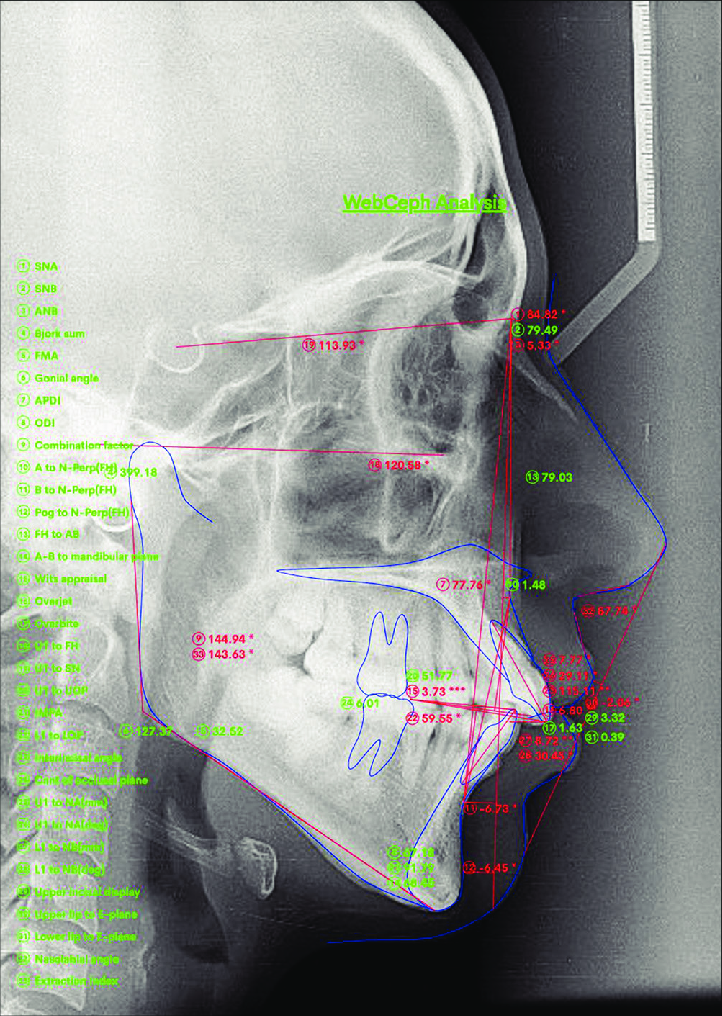

• ⁠⁠This is where it’s helpful to have an appointment with ortho or at least dentist, who can take a CBCT or x-ray to obtain your measurements. I did a rough, preliminary ceph analysis myself, all you need is a rule and protractor. Or you may have issues so large, they are obviously outside of the stated norms, no imaging necessary (for your investigative purposes anyway, down the line it definitely will be).

Lateral cephalogram showing WEBCEPH analysis

Lateral Cephalogram Showing WEBCEPH

View attachment 4444173